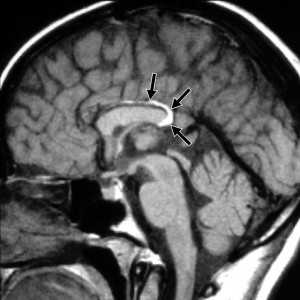

(а) МРТ, Т1-ВИ, сагиттальный срез: визуализируется типичная нейроэнтерическая киста в виде хорошо очерченного гиперинтенсивного объемного образования овоидной формы, локализующегося парамедианно кпереди от понтомедуллярного перехода.

(б) МРТ, Т1-ВИ, режим подавления сигнала от жира, аксиальный срез: у этого же пациента определяется, что объемное образование распространяется в нижнелатеральном направлении кпереди от нижних отделов продолговатого мозга. Центральные отделы объемного образования слегка смещены от срединной линии, что типично для нейроэнтерической кисты задней черепной ямки.

По данным МРТ, НЭК представляются хорошо ограниченными округлыми образованиями, сигнал от которых не меняется после введения парамагнетика (рис. 1). Рис. 1. НЭК с солидным компонентом в режиме FIESTA (наблюдение № 5). В режиме Т1 они изоинтенсивны или гиперинтенсивны (рис. 2), Рис. 2. Сагиттальный и фронтальный срезы МРТ в режиме Т1: киста изоинтенсивна ликвору (наблюдение № 5). в Т2 — гиперинтенсивны (рис. 3), Рис. 3. Аксиальные срезы МРТ головного мозга в режиме Т2: киста изоинтенсивна ликвору (наблюдение № 5). во FLAIR — гиперинтенсивны (рис. 4). Рис. 4. МРТ головного мозга до операции: определяется премедуллярное объемное образование, содержимое которого гиперинтенсивно ликвору в режиме Т2, гиперинтенсивно ликвору в режиме Т1, изоинтенсивно в режиме FLAIR, ствол головного мозга деформирован в переднезаднем направлении (наблюдение № 4). На К.Т. гиподенсны или изоденсны, не накапливают контрастное вещество (рис. 5). Рис. 5. КТ головного мозга до операции: премедуллярное новообразование изоинтенсивно ликвору (верхние снимки), в режиме перфузии выявляется отсутствие кровотока в нем (нижние снимки) (наблюдение № 7). В месте прилегания НЭК к стволу головного мозга возможно обнаружение солидного компонента, представленного секретирующим эпителием желудочно-кишечного тракта [1—4, 7, 8].

Данные нейровизуализации в нашей серии наблюдений суммированы в табл. 2. Таблица 2. Сравнительная характеристика нейровизуализационных данных Примечание. * — режим МРТ головного мозга Т1 с усилением сигнала парамагнетиком. ** — КТ головного мозга с контрастным веществом (КВ). Так, по данным МРТ головного мозга, образование в режиме Т1 изоинтенсивно или гиперинтенсивно ликвору (см. рис. 2), в Т2 гиперинтенсивно ликвору (см. рис. 3, 4, 6), в режиме FLAIR гиперинтенсивно ликвору (см. рис. 4), при внутривенном введении парамагнетика сигнал от него не усиливается (см. рис. 6). Рис. 6. МРТ головного мозга до операции: в режиме FLAIR премедуллярная киста гиперинтенсивна ликвору, в режиме Т2 гиперинтенсивна ликвору, в режиме Т1 с контрастом гиперинтенсивна ликвору, сигнал от нее не усилился после введения парамагнетика (наблюдение № 7). Следует отметить, что лучшим режимом МРТ, на котором визуализируются стенки кисты и солидный компонент (если он присутствует), является FIESTA (см. рис. 1).